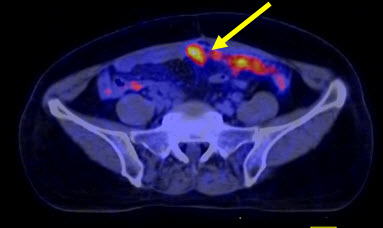

Hình 2. Bệnh nhân Lê Th. H., nữ, 58 tuổi, chẩn đoán: ung thư buồng trứng trái đã phẫu thuật và điều trị hóa chất năm 2011. Sau 8 tháng bệnh nhân kiểm tra thấy nồng độ chỉ điểm khối u CA 125 tăng cao (225ng/ml). Bệnh nhân được chỉ định chụp PET/CT kiểm tra. Trên hình PET/CT thấy tổn thương tái phát di căn màng bụng, trên hình CT không phát hiện được.